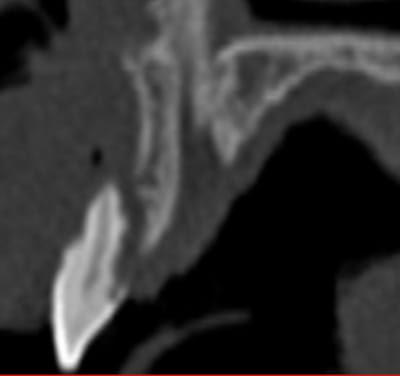

dans le même sujet, j'aurais aimé avoir votre avis sur ce cas. J'hésite entre une ROG avec membrane titane ou une greffe d'apposition.

04/11/2011 à 13h58

et pourquoi pas une expansion? tu as quoi, 14/15mm pour tes 2 implants? du fais 2 prémol? t'as pas besoin de diamètres super important amha...

j'ai 16mm entre les dents, mais 9mm de hauteur de crête pour la 47.

pour ce qui est de l'expansion, je n'ai jamais tenté l'exercice, et les corticales me paraissent bien épaisses.

Faut un peu de temps, mais çà parait pas impossible...

comme les 2 implants sont côte à côte tu bénéficies en plus de la longueur de la tranchée que tu peux faire pour avoir plus de "laxité" ( ou plutôt souplesse de l'os)...et la corticale semble moins dense là où tu as le plus besoin de faire de l'expansion...donc plutôt favorable

2 dents de 8mm çà fait 2 prémo...donc pas besoin d'avoir des implants très larges...des 4mm de diamètre doivent être suffisants...

Dans ce cas de figure, sans aucun doute, Régénération avec vis d'otéosynthèses ( en toile de tente) + membrane osseoguard résorbable.